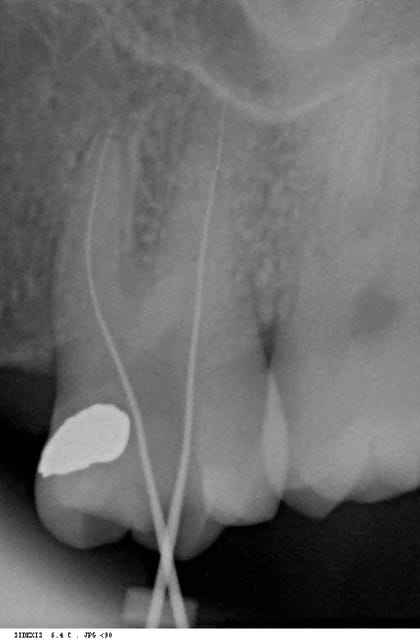

voilà une radio limes en places, de cette dent, avec une incidence différente.

personnellement, j'y vois ce qui ressemble fort à deux furcations et à deux racines mésiales. mais après tout, ce n'est qu'une rvg... je vois aussi le bout du deuxième canal, et je vois que sur le traitement terminé, je ne suis pas tout à fait au bout.

tout ça sur une dent au plancher intact...